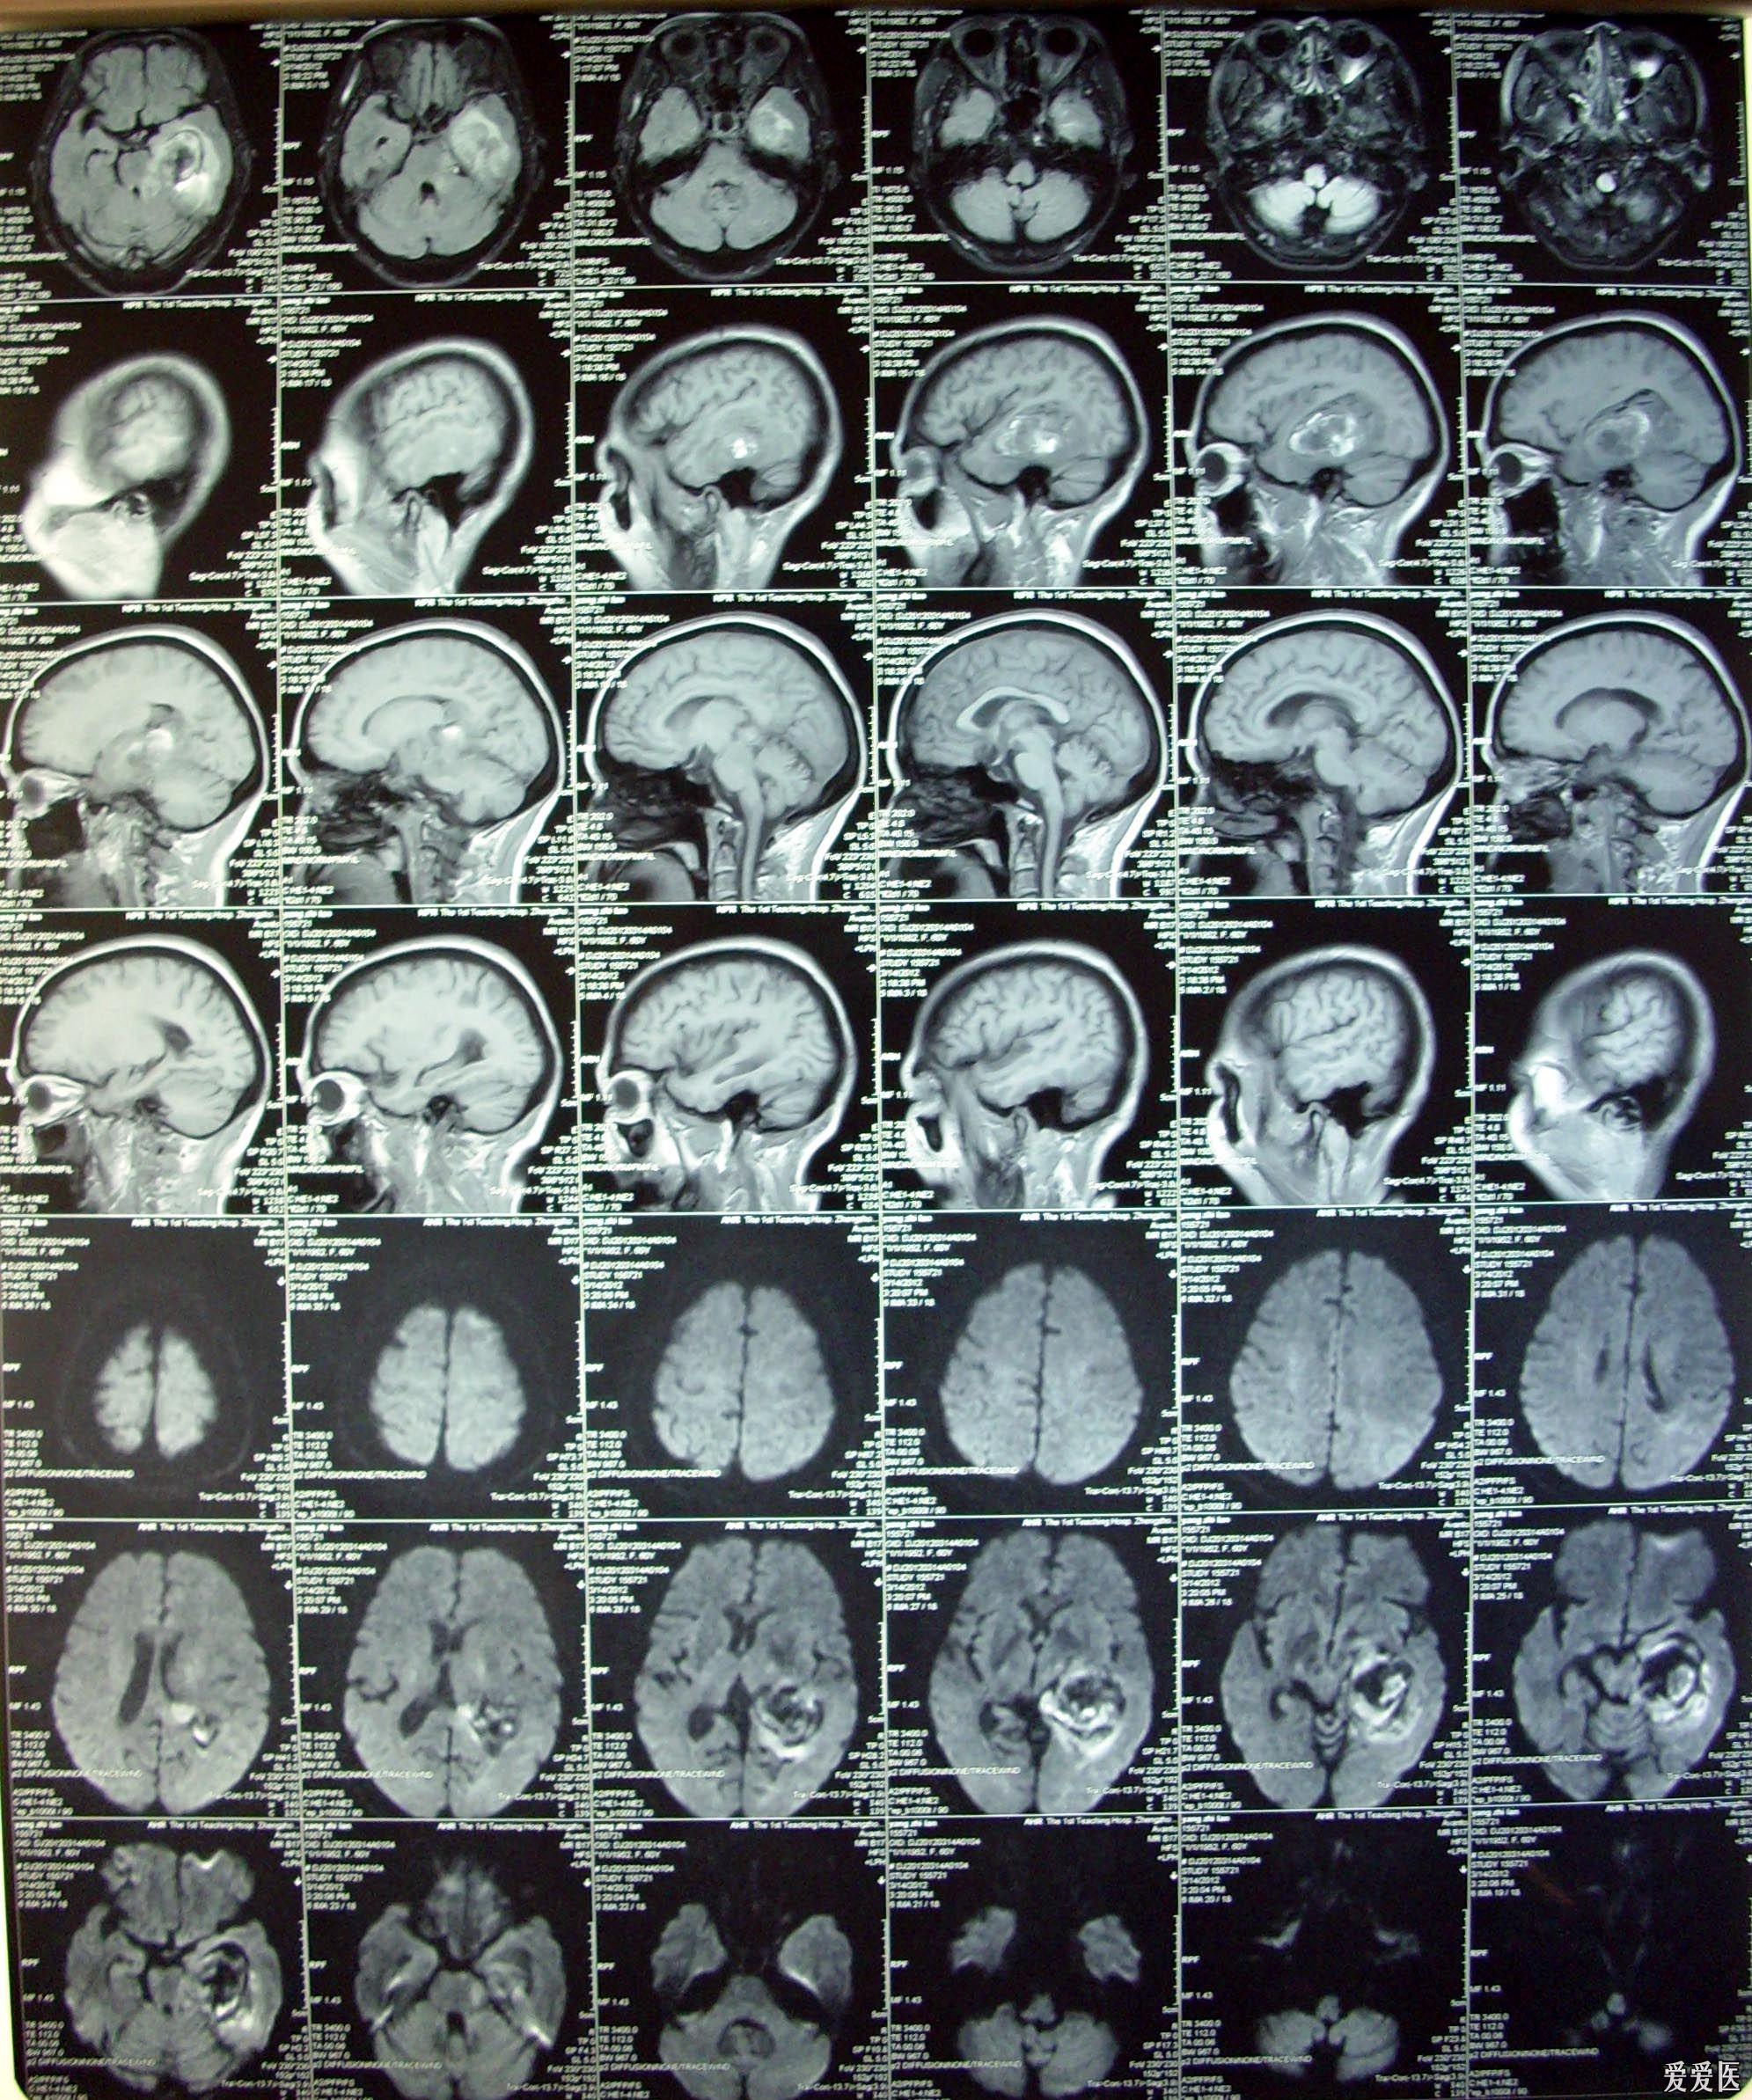

分享一例左侧颞叶星形胶质瘤的核磁影像

图片尺寸1280x676